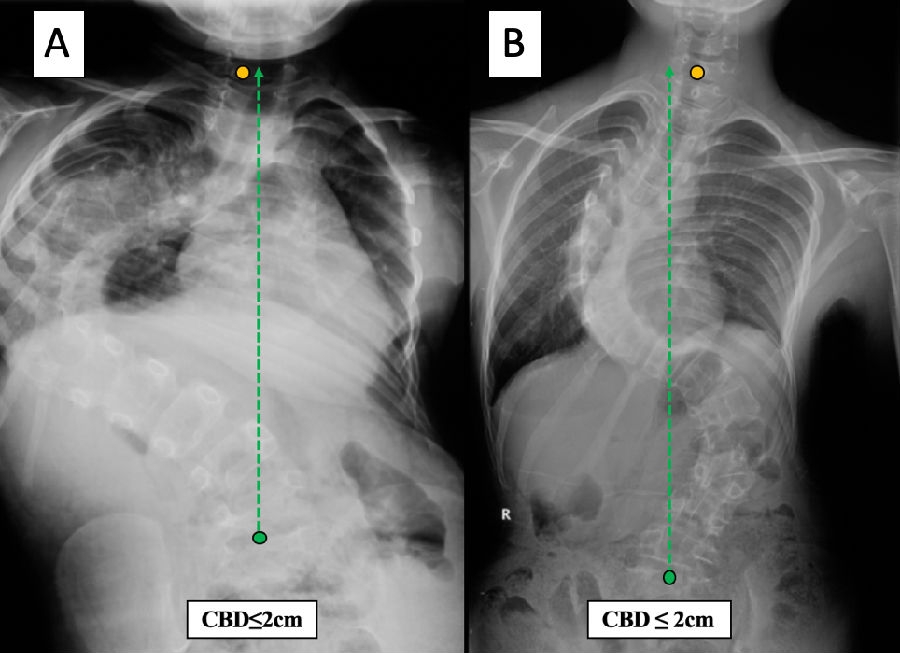

评估脊柱冠状面平衡最常采用的影像学参数为 C7铅垂线(C7 plumb line,C7PL)与骶骨中垂线(center sacral vertical line,CSVL)之间的水平距离(图1),即冠状面平衡距离(coronal balance distance,CBD)。对于AIS患者,脊柱侧凸研究学会(Scoliosis Research Society,SRS)将CBD≤2cm定义为冠状面平衡,将CBD>2cm定义为冠状面失平衡。对于成人脊柱畸形(adult spinal deformity, ASD)患者,Lowe等[1] 和Choi等[2]将CBD≥3cm定义为冠状面失平衡。通常地,将C7PL偏向CSVL左侧定义为“负”平衡,而C7PL偏向CSVL右侧定义为“正”平衡。

图1. 脊柱冠状面平衡CBD/CVA的测量方法

仔细观察可以发现,冠状面看似平衡的两个患者,如果弯曲类型不同,其真实的应力平衡也存在差异。例如,下面两位重度侧凸患者(图5),冠状面CBD均<2cm,但是A患者的躯干重心偏向CSVL一侧,而B患者胸弯和腰弯对称地分布在CSVL两侧,显然B患者在力学上处于更加平衡的状态。

图5. 两例CBD<2cm的重度脊柱侧凸患者

此外,对于冠状面失衡的两个患者,如果躯干重心的分布不同,其真实的应力情况也不尽相同。以下是两位CBD均>2cm的重度侧凸患者(图6),C患者上胸弯和胸腰弯分布在CSVL两侧,而D患者上胸弯、主胸弯和腰弯均分布在CSVL同一侧。同理,从重心分布的角度来看,C患者较D患者处于更加平衡的状态。

图6. 两例CBD>2cm的重度脊柱侧凸患者